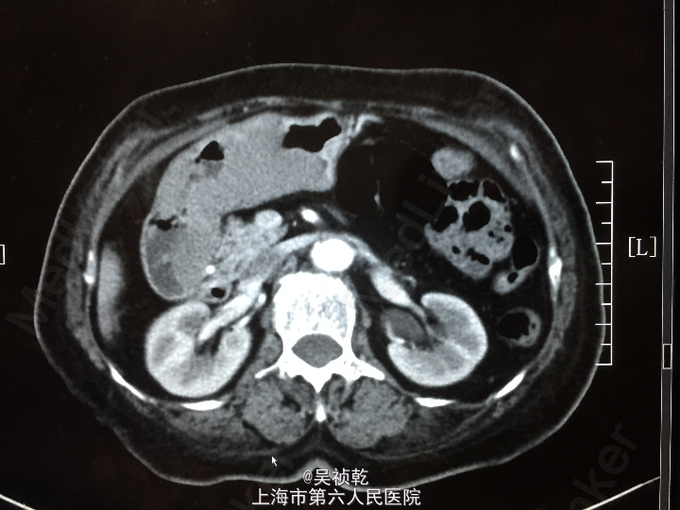

查体:T 36.8℃ P 85 次/分 R 24 次/分 BP 130/96 mmHg。神志清醒,呼吸平稳,皮肤粘膜无黄染,无贫血貌。全身浅表淋巴结未触及肿大。呼吸音清,未闻及干湿性啰音,部位双肺。心脏:心率80次/分,律齐,无杂音。腹部视诊:腹部平坦,右下腹可见手术疤痕,无腹壁挫裂伤或擦伤;触诊:腹壁柔软,全腹无压痛,无反跳痛;未触及肝,未触及脾。叩诊:无肝脏浊音界缩小或消失,无移动性浊音,肝区无叩痛,肾区无叩痛。听诊:肠鸣音正常。 辅查:2014-6-11 生化检验报告:总蛋白 64 g/L ,白蛋白 36 g/L ,白/球比例 1.3 ,谷丙转氨酶 7 U/L ,谷草转氨酶 15 U/L ,线粒体谷草转氨酶 7 U/L ,总胆红素 5.0 μmol/L ,直接胆红素 2.5 μmol/L ,总胆汁酸 4.4 μmol/L ,前白蛋白 147 mg/L ↓,尿素 4.7 mmol/L ,肌酐 60 μmol/L 。门诊化验检验报告:白细胞 4.0 *10^9/L ,红细胞 3.17 X10^12/L ↓,血红蛋白 82 g/L ↓,细胞比积 25.9 % ↓,血小板 371 X10^9/L ↑,中性细胞百分比 61.1 % 。门诊化验检验报告:凝血酶原时间 12.2 秒 ,国际标准化比率 1.11 ,部分凝血活酶时间 24.0 秒 ,纤维蛋白原 2.994 g/L ,凝血酶时间 21.6 秒 ↑。生化检验报告:血糖 4.54 mmol/L 。放免DPC(同位素)检验报告:甲胎蛋白(AFP) 4.60 ng/mL ,癌胚抗原(CEA) 2.01 ng/mL ,糖类抗原(CA125) 11.14 U/mL ,糖类抗原(CA199) 11.77 U/mL 。免疫检验报告:抗丙肝病毒抗体 阴性 。放免DPC(同位素)检验报告:游离T3 4.04 pmol/L ,游离T4 15.94 pmol/L ,促甲状腺激素 0.23 mIU/l ↓。2014-6-10 CT报告检查报告:1.胃窦部胃壁不规则增厚伴强化,符合胃癌表现,请结合临床。2.肝左内叶低密度灶,转移瘤可能,建议MRI增强进一步检查。3.肝内散在囊肿。CT报告检查报告:下腹部增强CT未见明显异常。2014-6-12 病房心超检查报告:左室、右室右房大小在正常范围。

入院后完善术前检查,胃镜及CT提示胃部肿瘤,胃癌可能,经积极术前准备,于2014.06. 16全麻下行胃癌根治术:患者麻醉达成后,平卧位,胃肠减压,留置导尿,常规消毒铺巾。切口:上腹部正中切口,上起剑突,下绕脐左侧达脐下3cm,切除剑突。进腹后探查:肝脏、腹膜、盆腔、肠系膜上血管根部及腹主动脉周围淋巴结(-)。远侧胃见胃窦大弯侧隆起型肿块,直径4*6cm,界不清,未累及浆膜,向远侧累及十二指肠。行胃癌根治术,D2。术野仔细止血,用43℃蒸馏水冲洗腹腔,给予法马新40mg+生理盐水100ml浸泡手术区域。吸尽后,于十二指肠残端及胃床放置引流,清点纱布、器械无误后,逐层关腹;术程顺利,术中出血约300ml,标本及淋巴结送病理,病人安返。术后病理检查报告:胃 ▉标本类型:根治性胃大部切除标本▉肿瘤部位:肿瘤位于胃窦及胃体,距上切 2.5CM,距下切 0.8CM▉大体类型:浸润型,大小: 11× 7 CM▉组织学类型:弥漫性大B细胞恶性淋巴瘤 ▉肿瘤浸润深度:全层 ▉血管浸润:(-),淋巴管浸润(+),神经周围浸润(+)▉切缘:上下切缘均未见肿瘤浸润▉区域淋巴结: 以下均见肿瘤浸润: 胃小弯LN5/8枚、胃大弯侧LN2/10枚。 以下均未见肿瘤浸润: (肝动脉旁)LN0/1枚。▉肿瘤旁病变:慢性胃炎 ▉淋巴结免疫反应状态:SH(+),PH(+),GH(+)▉肿瘤间质反应:淋巴细胞﹑浆细胞﹑组织细胞反应(+),纤维组织增生反应(+)胃窦及胃体:弥漫性大B细胞恶性淋巴瘤,肿瘤侵及胃壁全层。肿瘤组织免疫酶标记结果:CD20(+)、CD79a(+)、CD3(-)、CD5(-)、Bcl-2(+)、Bcl-6(+)、CD10(+)、Mum-1(-)、PAX-5(+)、CD30(-)、CD15(-)、Ki-67(80%+)、Her2(-)、CK(-)、LCK(-)、CK19(-)。 术后诊断更正为:胃弥漫性大B细胞恶性淋巴瘤。术后予以抗感染止血支持治疗,患者恢复尚可,术后予以进食后,患者反复呕吐,查胃镜及消化道造影,考虑胃动力不足,予以胃肠减压,促胃动力治疗,加强肠外营养,纠正水电解质失衡。术后患者出现肺炎予以抗感染治疗,肺部感染好转。7.16患者出现消化道出血、血象三系降低,血压降低、经止血、输血、升血小板对症治疗后仍未见明显好转;7.17并发呼吸功能不全,血压下降,予以呼吸支持,通畅气道,多巴胺升血压,考虑须行气管插管等有创抢救措施,家属签字放弃此类抢救措施。因血色素偏低,于7.16和7.17分别输红细胞2u、血浆200ml,无特别输血反应。2014-07-19凌晨1点患者出现血压下降,心脏停博,经抢救无效后死亡。